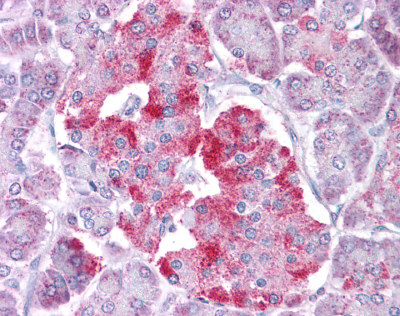

IHC (Immunohiostchemistry)

(Rabbit Anti-STAT1 AntibodyParaffin Embedded Tissue: Human KidneyCellular Data: Epithelial cells of renal tubuleAntibody Concentration: 4.0-8.0 ug/mlMagnification: 400X)